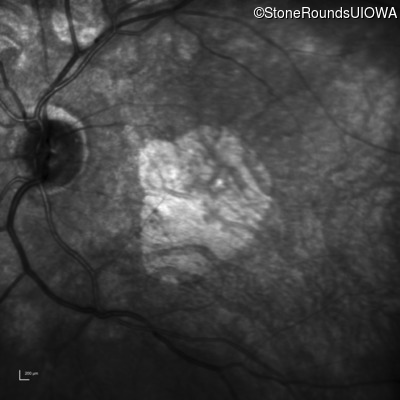

Infrared Fundus Photograph - Right - 20/100

Exemplar